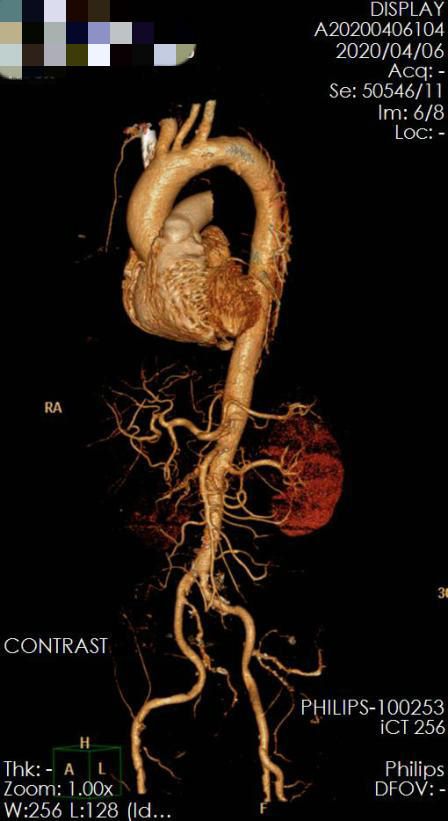

来到五附院后,值班大夫赶紧带他做了个胸腹主动脉CTA,结果确诊胸主动脉夹层,血管内膜从左侧锁骨下动脉以远一直撕到右侧髂动脉,幸运的是夹层大部分假腔已经大部分血栓化,但是仍有破口血流进入,而且没有影响重要的内脏动脉。CTA检查还发现了一个关键问题,右侧肾动脉重度狭窄,患者高血压考虑为继发性高血压,平日血压控制不好极有可能是这个原因。

▲ 图1 入院CTA胸主动脉夹层,假腔大部分血栓化,仍有血流经破口流入假腔